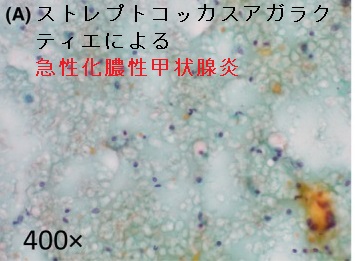

甲状腺機能低下症と糖尿病は免疫不全で日和見感染や感染症の重症化がおこる。非定型抗酸菌、緑膿菌、ストレプトコッカスアガラクティエ(B群溶血性連鎖球菌の一種)で急性化膿性甲状腺炎。マイコバクテリウム・マリナムは最多の非定型抗酸菌感染症で熱帯魚や水槽から感染。無顆粒球症では緑膿菌(Pseudomonas aeruginosa)敗血症。レジオネラ菌はエアコン・加湿器(特に家庭用超音波式加湿器)・水場・循環式風呂/温泉が感染源になり集団感染。レジオネラ肺炎は大葉性肺炎。ストレプトコッカスアガラクティエは新生児髄膜炎、子宮内感染、敗血症/内因性眼内炎、感染性心内膜炎。

ストレプトコッカスアガラクティエによる急性化膿性甲状腺炎の報告があります[Clin Case Rep. 2017 Jun 19;5(8):1238-1242.]